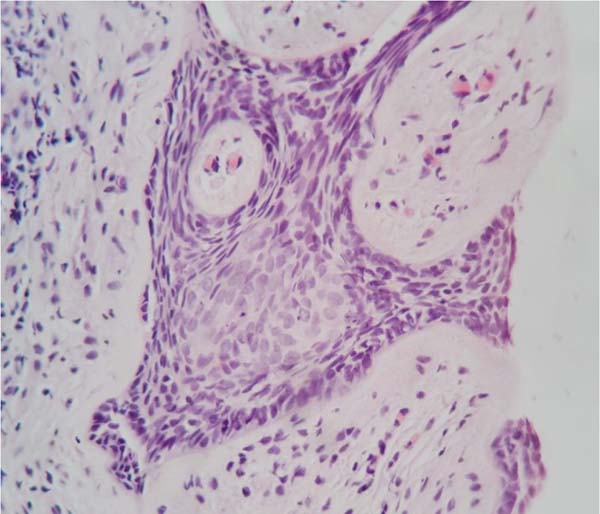

Uma ultrassonografia transvaginal e uma vulvoscopia foram indicadas. Identificouse, respectivamente, pequeno cisto simples no ovário esquerdo e lesão hipercrômica de superfície lisa no grande lábio esquerdo, suspeita de neoplasia. O histopatológico do material da biópsia incisional da lesão (Figura 2) mostrou tratar-se de provável carcinoma basocelular nodular, com invasão da derme e sem invasão perineural.

A paciente submeteu-se a uma ressecção do tumor da vulva com margens macroscópicas livres e sutura primária. Na cirurgia, não houve complicações e a alta foi obtida após uma noite após o procedimento. No pós-operatório imediato e tardio, também não ocorreram intercorrências, como deiscência e/ou inflamação. O histopatológico da peça cirúrgica (Figura 3) mostrou um carcinoma basocelular nodular com área irregular, plana, branco, medindo 0,7x0,4cm, com as margens laterais distando 7,0 e 5,0mm e as profundas, 5,9 mm; todas livres. A paciente, 14 meses após a cirurgia, encontra-se sem evidência de recorrência local ou regional.

O diagnóstico é feito por biópsia com auxílio da análise histopatológica por meio dos corantes hematoxilina e eosina ou a detecção de marcadores típicos por imuno-histoquímica, com o CK20 sendo o mais indicado, que não foi realizada em nosso caso pelo caráter mais morfológico dos achados, podendo gerar questionamento, e sendo mais utilizada com finalidade acadêmica. A apresentação pode confundir com outras doenças, como psoríase, dermatite, líquen escleroso, neoplasias intraepiteliais vulvares e doença de Paget1,3.